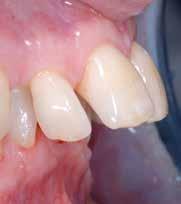

B.M. Bambina di sei anni e mezzo, con malocclusione scheletrica di II Classe, deep-bite over-jet elevato, lieve contrazione dell’arcata superiore, alterazione dell’eruzione dell’elemento dentale 21.

Fig. 123 > Immagine intraorale laterale destra.

Fig. 124 > Immagine intraorale laterale sinistra.